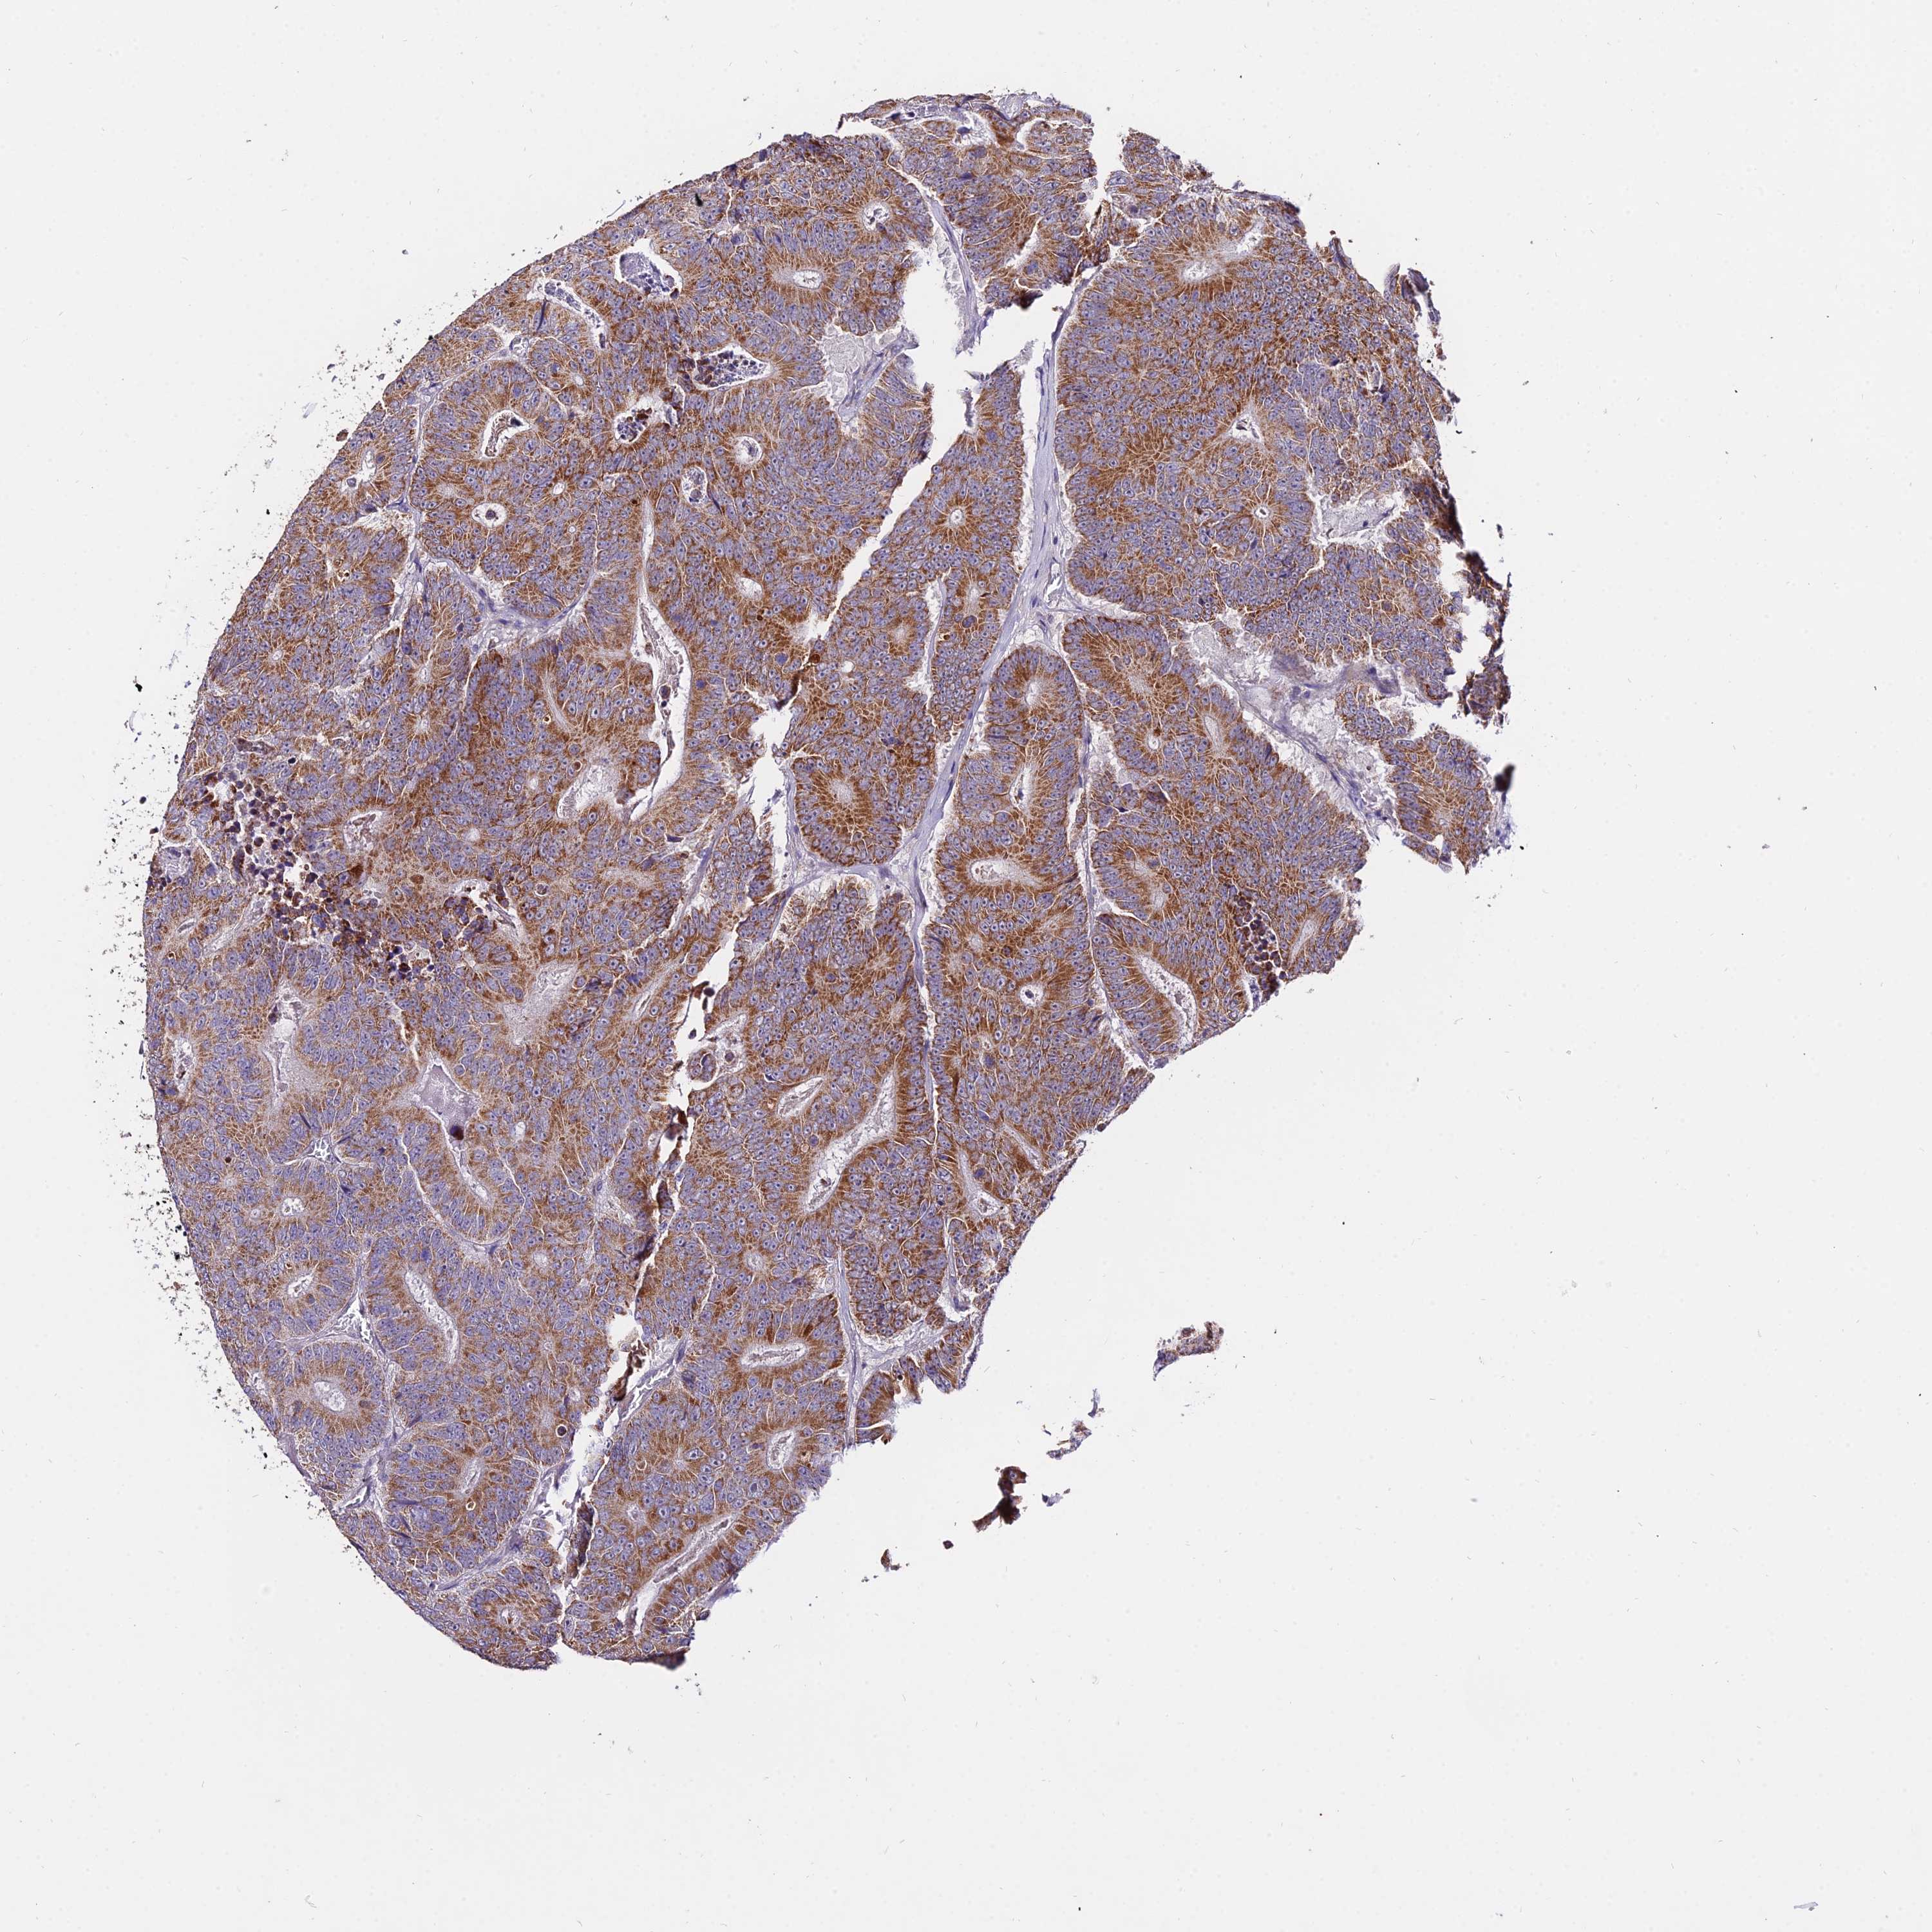

CANCER COLORECTAL CANCER Show tissue menu

Colorectal cancer

Human cancer

Colon adenocarcinoma